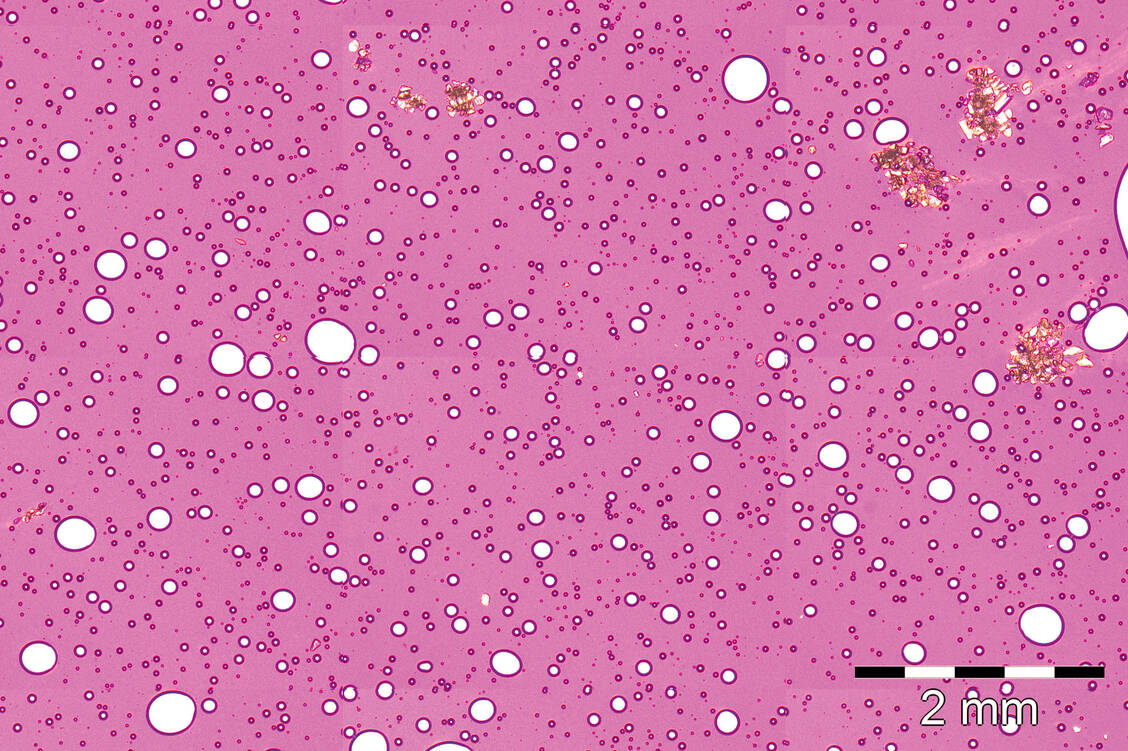

Die Bestimmung der Partikelgröße erfolgte mittels Optischer Mikroskopie (Ph. Eur. 9.0, 2.9.37) im polarisierten Licht. Die Beurteilung erfolgte in Anlehnung an die damalige Version der DAC Monographie M-132 Metronidazol-Verreibung 10 Prozent mit Nicht­ionischer hydrophiler Creme SR sowie den Kommentar zum Europäischen Arzneibuch zur Monographie Halbfeste Zubereitungen zur Anwendung auf der Haut (12, 13). Untersucht wurden pro Creme jeweils bis zu fünf aus der Zubereitung gezogene Proben.

Folgende Akzeptanzkriterien wurden festgelegt:

• Maximal 2 Partikel > 50 µm und ≤ 90 µm

• Maximal 1 Partikel > 90 µm und ≤ 180 µm

• Kein Partikel > 180 µm

Häufig wurden in der mikroskopischen Untersuchung sehr große Partikel in Form von Kristallen und/oder Agglomeraten über > 180 µm gefunden (Abbildung). Betroffen waren alle Herstellungsverfahren entsprechend der Häufigkeit ihres Einsatzes im Ringversuch mit einem leichten Vorteil für die Herstellung mittels Fantaschale und Pistill. Es stellte sich heraus, dass auch Zubereitungen, die kurz nach dem Eingang im ZL keine Auffälligkeiten bei der Partikelgrößenuntersuchung zeigten, nach etwa zwei Wochen bei einer erneuten Überprüfung zu Testzwecken große Kristalle aufwiesen. Das heißt, dass, bedingt durch hohe Temperaturen beziehungsweise Temperaturschwankungen während des Transportes zum ZL, eine nachträgliche Kristallbildung außerhalb des Einflussbereichs der Apotheken nicht ausgeschlossen werden konnte. Aus diesem Grund wurde bei rund 350 Teilnehmern, deren Herstellung zwischen Mai und August 2017 stattgefunden hatte, der Prüfparameter Partikelgröße nicht bewertet.